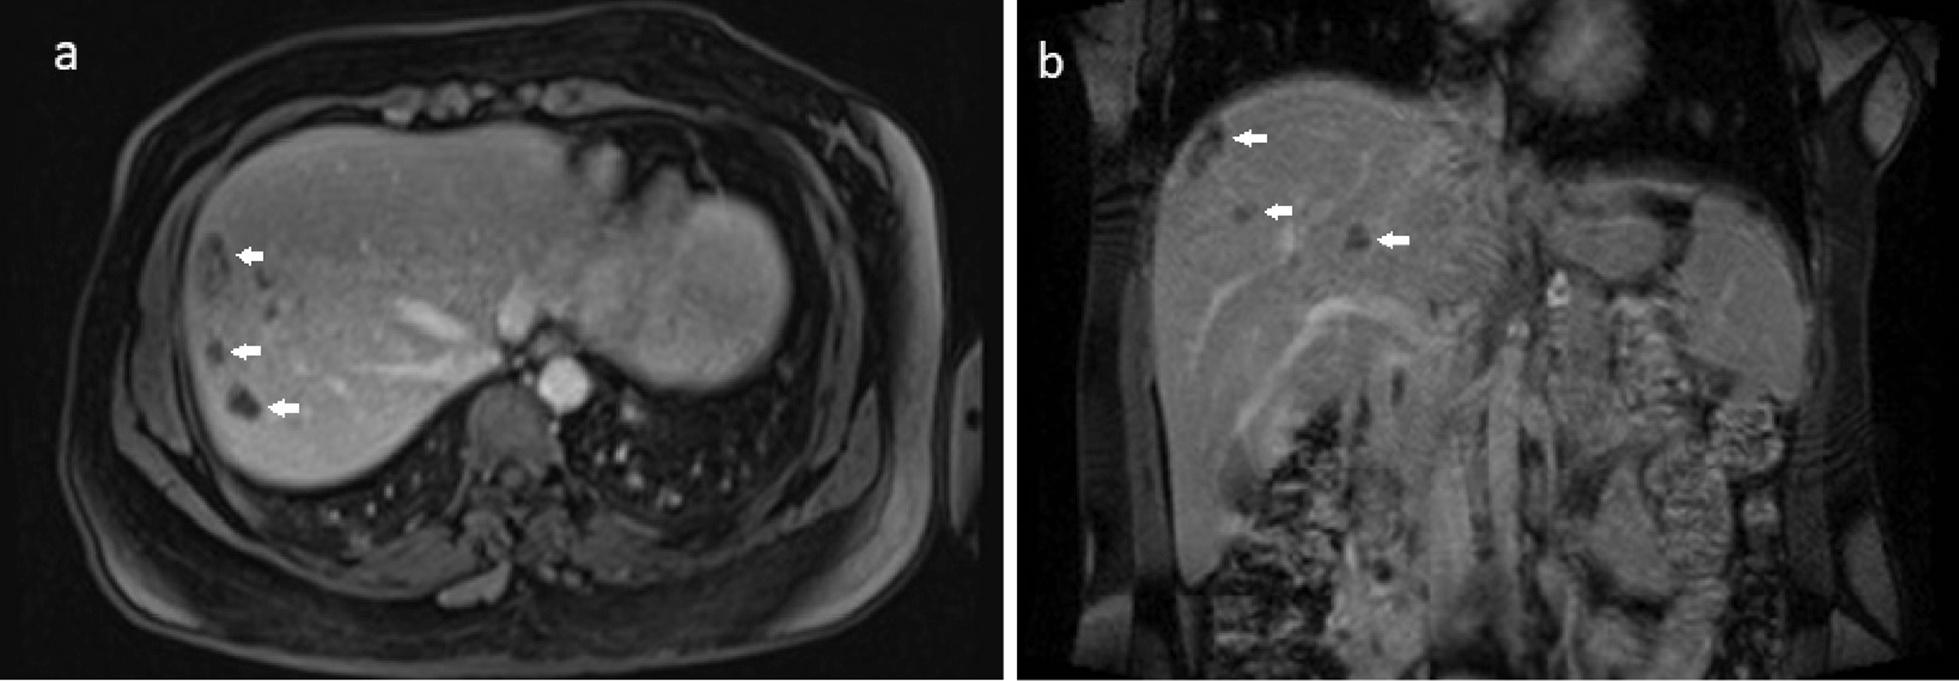

We report the case of a 35-year-old Iranian patient who presented with right upper quadrant pain, low-grade fever, fatigue, and anorexia. The patient had a history of recent travel to the Gilan Province of Iran, almost a month before the onset of symptoms, which is an endemic area of fascioliasis in the country. Laboratory examinations revealed eosinophilia, elevated hepatic enzymes, and slightly raised C-reactive protein. Contrast-enhanced computed tomography of the patient shows clusters of focal ill-defined hypodense lesions with mild peripheral enhancement in the right liver lobe and subcapsular regions. Magnetic resonance imaging of the liver revealed multiple ill-defined lesions of low signal intensity on the T1-weighted image and high signal intensity on the T2-weighted image, extending from the liver capsule into deeper parenchyma toward periportal regions, which shows mild peripheral enhancement on post-contrast images. Imaging-based diagnosis of fascioliasis was made depending on the characteristic distribution of subcapsular tracts/lesions on the above-mentioned imaging, which was then confirmed by serologic tests using enzyme-linked immunosorbent assay. The patient was treated with triclabendazole, showing great clinical improvement, and was eventually discharged in good health condition.

我们报告了一名 35 岁的伊朗患者的病例,该患者出现右上腹疼痛、低热、乏力和食欲不振。患者最近有前往伊朗吉兰省的旅行史,在症状出现前将近一个月,该国的该地区是片形吸虫病的流行区。实验室检查显示嗜酸性粒细胞增多、肝酶升高和 C 反应蛋白略有升高。患者的增强 CT 显示右肝叶和包膜下区域有簇状局灶性边界不清的低密病灶,伴轻度周边强化。肝脏磁共振成像显示多个边界不清的病灶在 T1 加权像上呈低信号强度,在 T2 加权像上呈高信号强度,从肝包膜向深部实质延伸至门脉周围区域,在增强后图像上显示轻度周边强化。根据上述影像学上特征性的包膜下轨迹/病变分布,做出片形吸虫病的影像学诊断,然后通过酶联免疫吸附试验进行血清学检测来证实。患者接受三氯苯达唑治疗,临床症状显著改善,最终健康状况良好出院。